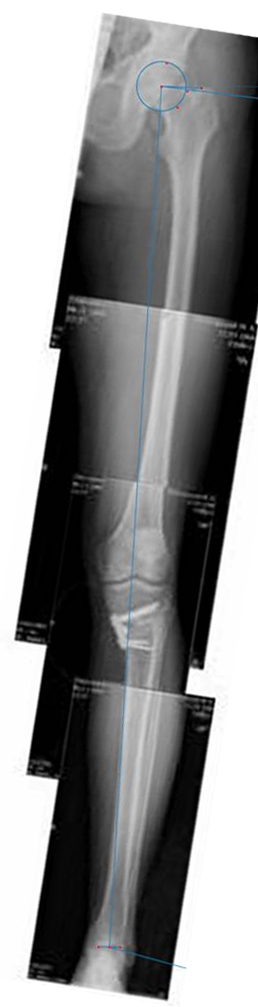

[Ortho] высокая тибиальная остеотомия

Имя     : Ортофорум 1.jpg